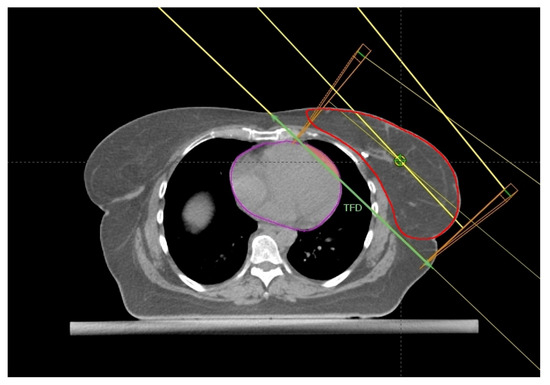

2.2. The Cardiac Contact Distance in the Axial (CCDax) and Parasagittal (CCDps) Planes and the Lateral Heart-to-Chest Distance (HCD)

2.5. Maximum Heart Depth and Tumor Bed Site